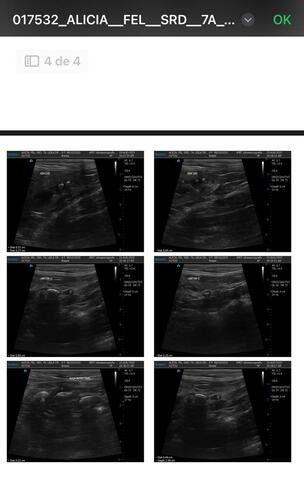

Após vários exames de ultrassom e medicação para dilatar os ureteres nos quais ela tem as pedras, como tentativa de não submetê-la á cirurgia, não tivemos sucesso. Sendo realmente necessária a cirurgia para remoção das pedras.

A Alicia foi diagnosticada com doença renal crônica e está enfrentando um quadro muito grave: ela tem muitas pedras nos dois rins e uma obstrução séria no ureter direito, o que está comprometendo sua saúde de forma crítica.O único caminho possível para salvá-la é através de uma cirurgia delicada chamada "ureter bypass", que custa entre R$ 15 mil e R$ 25 mil reais, incluindo todos os gastos como internação, medicamentos, alimentação, exames, transporte entre outros gastos — um valor que está completamente fora das minhas possibilidades no momento.